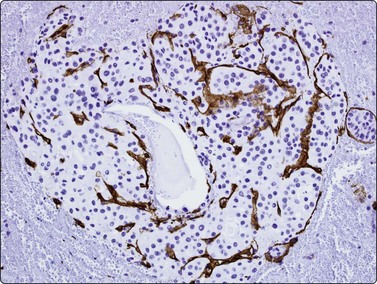

image

Fig. 10.25 Hepatocellular carcinoma

CD34 immunostaining demonstrates the classic endothelial staining pattern which is absent in reactive liver cell block (CD34, HP).

Prior to embarking on costly immunotests, a reticulin stain can highlight loss of a normal sinusoidal pattern and shows either widened trabeculae, rounded islands and pseudoglands or just a reduction or total absence of reticulin and distinguish benign from malignant liver lesions (see Figs 10.6 and 10.16).77-79120

CD34 and factor VIII immunostaining have been used in demonstrating the classic endothelial staining pattern of HCC (Fig. 10.25), absent in reactive liver and metastatic carcinoma,139 but are limited by partial staining of adenoma and focal nodular hyperplasia. Indeed, they provide little more information than the less expensive reticulin.131,139-141 Over-expression of Glypican-3, a heparan sulphate proteoglycan that plays an important role in cell growth and differentiation, has been observed in malignant hepatocytes. In several studies on cytological smears, positive staining for Glypican-3 showed a high sensitivity (80–90%) and specificity (> 95%) in HCC versus metastatic tumors and benign liver lesions.142-144